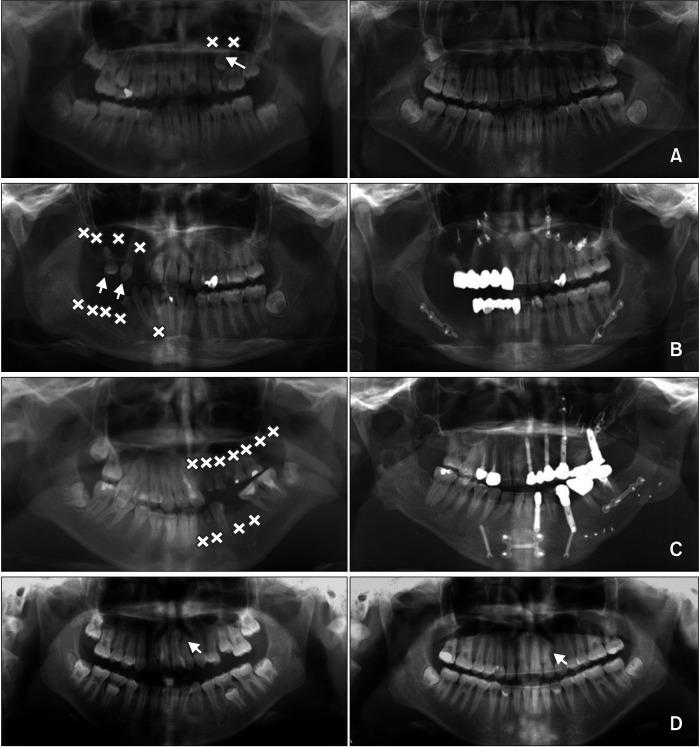

The samples consisted of 10 PRS patients, who were treated and/or followed-up at Seoul National University Dental Hospital between 1998 and 2019. Using a novel PRS severity index based on the numbers of the atrophy-involved area and asymmetry-involved item, we classified them into mild (n = 3), moderate (n = 2), and severe (n = 5). Dental phenotypes, including congenitally missing tooth (Con-Missing-Tooth), microdontia, tooth with short root (Short-Root), tooth with dilacerated root, and delayed eruption/impacted tooth, were investigated along with Tx-Mod.

RESULTS

The side of occurrence of all dental phenotypes showed 100% concordance with the side of PRS involvement. The most two common dental phenotypes were Con-Missing- Tooth and Short-Root (n = 29 and n = 17 in six patients). The sums of the average number of Con-Missing-Tooth and Short-Root increased from mild PRS to moderate PRS and severe PRS cases (1.0, 6.0, and 6.2). In terms of Tx- Mod, growth observation due to mild atrophy, fixed orthodontic treatment, and grafting were used for mild PRS cases. Tx-Mod for moderate PRS cases involved growth observation for surgery due to an early age at the initial visit. For severe PRS cases, diverse Tx-Mod combinations including unilateral functional appliance, fixed orthodontic treatment, growth observation, grafting, and orthognathic surgery were used.

方法

样本包括10例PRS患者,于1998年至2019年期间在首尔国立大学牙医院接受治疗和/或随访。我们基于萎缩累及区域数量和不对称累及项目构建了一个新的PRS严重程度指数,将患者分为轻度(n = 3)、中度(n = 2)和重度(n = 5)。对牙齿表型进行了研究,包括先天性缺牙(Con-Missing-Tooth)、过小牙、短根牙(Short-Root)、牙根弯曲牙以及萌出延迟/阻生牙,并分析了相应的Tx-Mod。

结果

所有牙齿表型的发生侧与PRS累及侧的一致性为100%。最常见的两种牙齿表型是先天性缺牙和短根牙(6例患者中分别为29颗和17颗)。先天性缺牙和短根牙的平均数量总和从轻度PRS到中度PRS再到重度PRS病例逐渐增加(分别为1.0、6.0和6.2)。在Tx-Mod方面,轻度萎缩患者进行生长观察,轻度PRS病例采用固定正畸治疗和植骨术。中度PRS病例的Tx-Mod包括因初诊年龄小而进行手术生长观察。对于重度PRS病例,采用了多种Tx-Mod组合,包括单侧功能矫治器、固定正畸治疗、生长观察、植骨术和正颌手术。